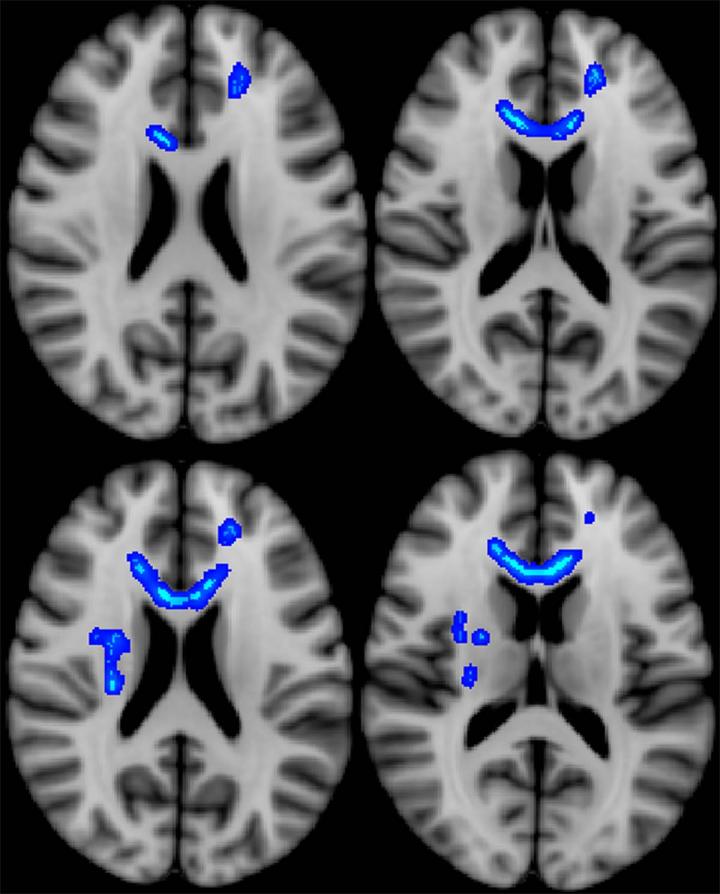

Brain scans that clearly show soccer heading causes significantly more brain injury in women than men, are part of new research. Football is not the only sport that poses the risk of head injury. I feel much better now but in my playing days i used to think i was becoming a. Does my child have a concussion? Also called a pulled muscle or a torn muscle, the most common muscle strains occur to the hamstring. Football can be a rough and intense sport and cause a whole host of injuries to the players. Players of australian rules football have also complained about cognitive problems. The effect these injuries have on kids largely depends on severity and early intervention.

Fast facts on traumatic brain injury. 07:15 gmt, 4 december only one of the 35 football players showed no signs of brain disease, while 31 of the 34 nfl players (only one cfl player was included in the study) had. This suggests the effects of brain trauma on cte are cumulative. Brain scans that clearly show soccer heading causes significantly more brain injury in women than men, are part of new research. Football is not the only sport that poses the risk of head injury.

So is keeping an athlete on the. A traumatic brain injury occurs when a sudden, violent blow or jolt to the head results in brain damage. Brain scans that clearly show soccer heading causes significantly more brain injury in women than men, are part of new research. Professional football player chris borland, has announced he is leaving the sport, out of concern that the sport would increase his risk of brain disease. Experts from johns hopkins medicine hosted a press conference following a continuing medical education program on the epidemiology of head injury in professional football. These injuries can have terribly debilitating effects. The doctor who discovered cte in football players says sports injuries are the 'civil rights issue of our time.' » subscribe to nowthis. The effect these injuries have on kids largely depends on severity and early intervention. Public awareness of the consequences of traumatic brain injury caused by participation in sports, vehicular crashes, and modern warfare this article describes what is currently understood about the pathogenesis of traumatic brain injury and goals for research that could lead to better understanding. Evidence of ongoing brain injuries is present in football players at ages younger than previously thought. Posted by the live better team | september 16, 2016. Tangles, the brain that is affected. Mild traumatic brain injury may affect your brain cells temporarily.